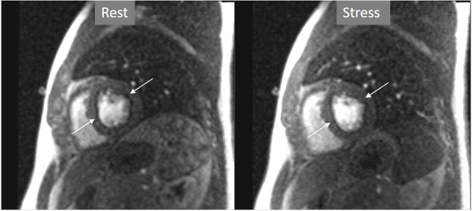

A not infrequent finding is a diffuse, annular, transient, subendocardial defect not present at rest (Fig. 9), which, in the absence of any recognizable obstructive lesion in an epicardial coronary artery, has been deemed to correspond to diffuse microvascular dysfunction (MVD) [41, 42]. CMR perfusion is sensitive to both the downstream effects of discrete epicardial stenoses and those due to disturbances of coronary microcirculation, and subendocardial hypoperfusion is on the pathophysiological basis of each one. For this reason, theoretically, a global, inducible subendocardial defect, could also be due to multivessel epicardial disease with balanced ischemia. In practice, however, this latter instance presents with extensive but heterogenous defects in terms of intensity, persistence and transmurality and, not rarely, also with perfusion defects at rest (Fig. 10A). Importantly, an accompanying induced contractile disfunction may be found in particularly impaired regions (Fig. 10B), a finding which is never seen in MVD.

Fig. 9.Microvascular defect. Circumferential subendocardial perfusion defect at stress, not present at rest, in the absence of LGE, in a patient without significant epicardial coronary lesions at angiography (right panels).